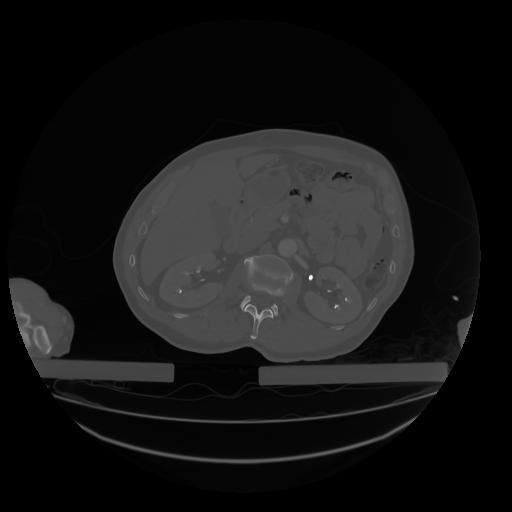

28 CUERPO,CE,Vol,2.0,CUERPO,,